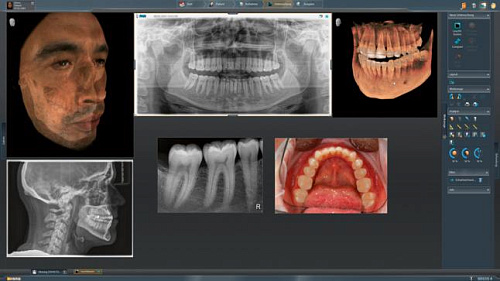

Диагностика последнего поколения, идеально решающая задачи рентгеновского обследования независимо от размеров клиники. Поля изображения зависят от определенной клинической картины, поэтому специалистам так удобно работать с ORTHOPHOS SL 3D. Данная установка делает объёмные картинки для одиночной реставрации в 3D качестве полностью всей челюсти такого размера, которого требуется.

Планирование одиночной реставрации, эндодонтические исследования и пр. – для этого специалист может выбрать объёмные варианты 8 х 8 см или 11 х 10 см, также предлагается объём 5 х 5,5 см. Снимки в HD-качестве, стандартные настройки или выбор объёма обследования в зависимости от диагноза — всё это врач получает в отличном качестве, а для пациента излучение в районе исследования минимально.

С технологией SL можно за один сеанс получить огромное количество снимков. Те из них, где фокусировка наиболее чёткая, автоматически соединяются. В итоге одна процедура — снимки челюсти полностью в самом лучшем качестве. Даже нестандартные случаи не станут помехой в обследовании. К примеру, при ретинированных зубах уже после того, как снимок сделан, нужную область можно выделить подробнее, и в ещё одном рентгене необходимость отпадает.

Программное наполнение для работы с изображениями с модулем MARS*

Металлические элементы в ротовой полости могут привести к возникновению помех на снимке. Благодаря наличию программного обеспечения MARS наличие объектов из металла определяется автоматически, влияние артефактов нивелируется. Таким образом не требуется повторного изображения для уточнения диагноза.

Модернизированный сенсорный экран Easypad с понятным и удобным интерфейсом позволяет выставить наилучшие параметры контрастности и разрешения. Систематизация данных по диагностике становится значительно удобнее и проще с ПО обработки изображений SIDEXIS 4, ORTHOPHOS.

1. Двух-и трёхмерные снимки совмещаются в одной программе

2. В одном окне можно сравнивать разные 3D-результаты

3. Считанные минуты уходят на просмотр анамнеза пациента.